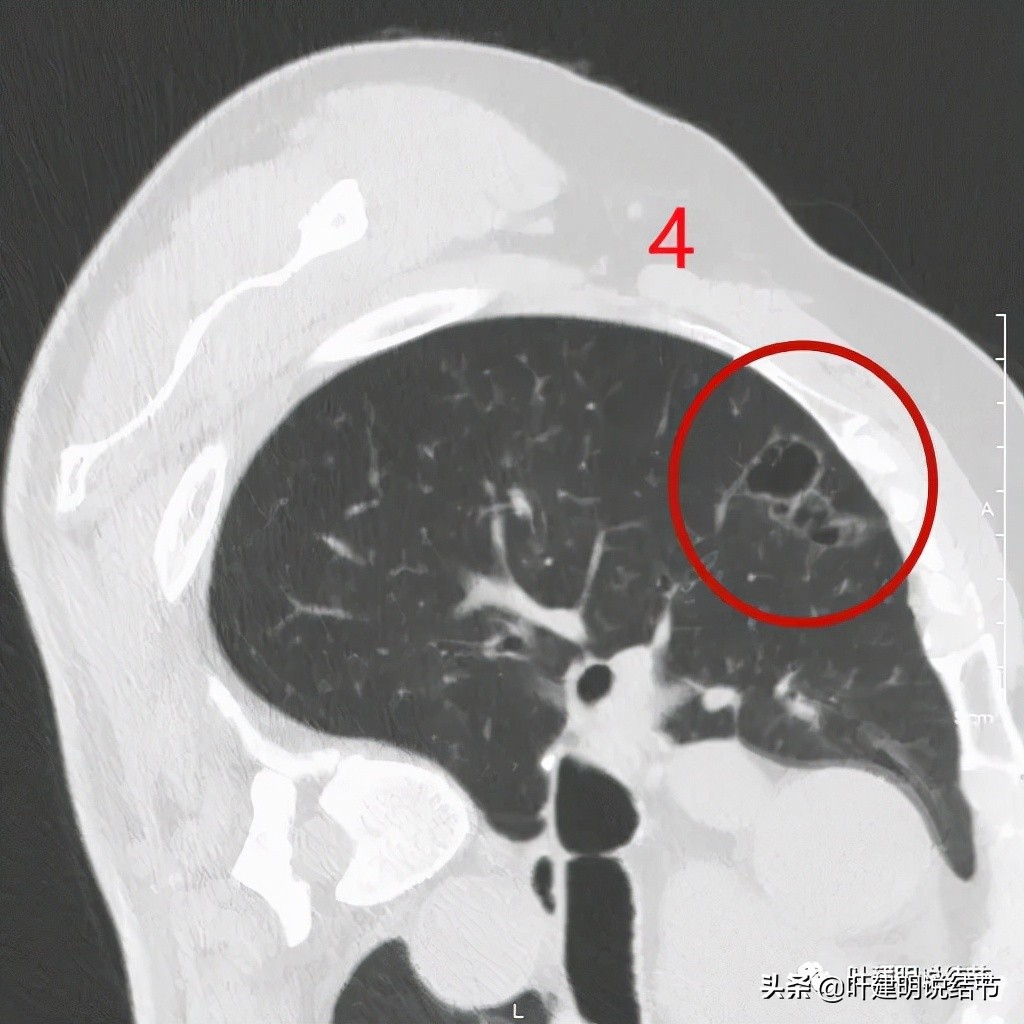

以上诸图是病灶4:考虑囊腔型肺癌可能性大,壁厚薄不均,内壁不光滑,有血管进入病灶,有少许密度偏高的成分,但纵隔窗上未见,不是真正意义上的实性成分。

感觉怎么囊壁实性成分密度有点显得高,粉色箭头所示处明显密度不均,偏高密度;蓝色箭头示有胸膜牵拉;砖色箭头示分叶征;桔色箭头示血管走向病灶。我觉得关键是病灶位置好,紧贴胸壁,能局部楔形切除,对肺功能影响小,又能去除危险。倾向切了它!